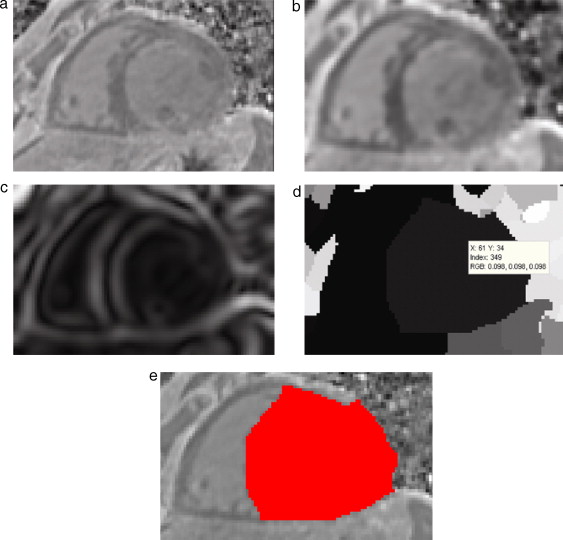

En la figura 12 , se presenta la aplicación de esta rutina para segmentar la zona de la aorta descendente en la reconstrucción 3D de IRM cardiovascular. En la figura 12 .a se presenta uno de los cortes de la imagen original, en la cual se observa la implantación de un snake inicial en la zona de la aorta. En la figura 12 .b se observa la imagen mapa de distancias generada luego de aplicar el algoritmo Level Set , obsérvese que los voxels dentro de la región de la aorta tienen valores de intensidad más oscuros comparados con aquéllos que se van alejando de esta zona, cuyos valores de intensidad son más. En la figura 12 .c se observa en color rojo la zona de la aorta segmentada, la cual fue obtenida con umbralización al seleccionar los voxels de la figura 12 .b con niveles de gris cercanos de cero.

Segmentación de aorta descendente empleando Level Set. (a) Vista de un corte ...

Figura 12.

Segmentación de aorta descendente empleando Level Set . (a) Vista de un corte axial de IRM cardiovascular con la implantación de un snake en la zona de la aorta. (b) Imagen mapa de distancias obtenida luego de aplicar la técnica Level Set . (c) Selección de la zona de aorta extrayendo la función zero level (d) Vista 3D de la aorta descendente segmentada.

En la figura 15 se presentan los resultados obtenidos por cada etapa de procesamiento en IRM cardiovascular. Las imágenes médicas utilizadas tienen formato DICOM [39] , con 59 cortes de tamaño 192 × 192 pixels, voxel spacing: 1,5625 × 1,5625 × 2,5 mm . Por efectos de visualización, solamente se presenta uno de los cortes axiales de la imagen 3D.

Preproceso y segmentación el volumen del ventrículo izquierdo. (a) Corte axial ...

Figura 15.

Preproceso y segmentación el volumen del ventrículo izquierdo. (a) Corte axial de la IRM cardiovascular original. (b) Imagen (a) filtrada con difusión anisotrópica. (c) Imagen gradiente obtenida a partir de (b). (d) Imagen Watershed con segmentos etiquetados obtenida a partir de (c). (e) Selección del segmento del ventrículo izquierdo empleando umbralización.